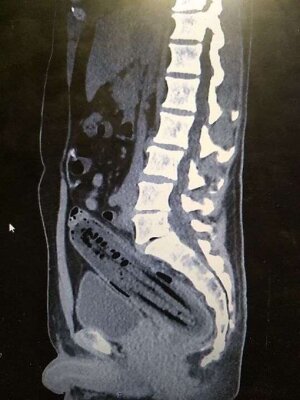

Одним из лидеров недели в Twitter стал хештег #WeirdThingsToPutUpYourAss (Странные штуки, которые суют в задницу). Проктологи со всего мира поделились рентгеновскими снимками содержимого анусов своих пациентов. Выяснилось, что огурец - еще не самое удивительно, что можно обнаружить там, где не светит солнце.